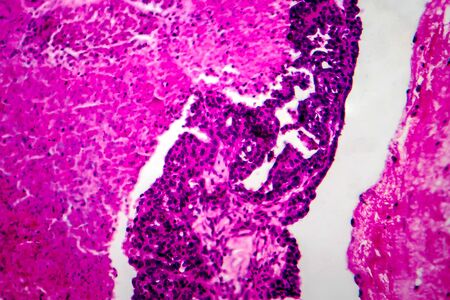

Bowen's Disease Tumor under the microscope 100x

Bowen's Disease Tumor under the microscope 100x